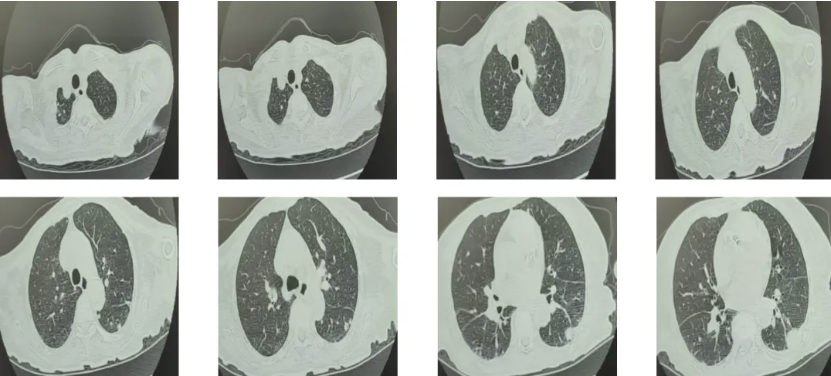

图2 我院12.19颅脑MRI平扫+增强

左侧顶叶见小斑点状DWI高信号(急性-亚急性脑梗塞可能);大脑半卵圆区、基底节区可见多发斑点状、斑片状长T1、长T2信号,部分病灶T2-FLAIR上呈稍高信号,部分沿侧脑室旁晕状分布,增强扫描未见强化。双侧额顶部少许硬膜下积液(宽约0.8cm)。增强扫描显示双侧脑膜明显线样强化,符合脑膜炎改变:脑实质未见明显异常强化灶。部分脑室、沟、池增宽,脑中线结构居中。

2025-12-19(入院第19天):完善腰椎穿刺,脑脊液常规:轻度血性,浅红色,潘迪氏试验阳性,红细胞22900×10^6/L,白细胞67×10^6/L(单个核57%,多个核43%)。脑脊液生化:葡萄糖5.82mmol/L,氯109mmol/L,ADA 3.50U/L,总蛋白2243mg/L。墨汁染色未检出隐球菌。同步血糖14.50mmol/L。颅脑MRI平扫+增强提示脑膜炎可能。

结合影像学进展、三系减低、铁蛋白显著升高、LDH持续>1000U/L,考虑结核性脑膜炎不能排除,于2025-12-19开始诊断性抗结核治疗:甲泼尼龙40mg→80mg;异烟肼300mg qd;利福平0.45g qd;吡嗪酰胺0.5g bid;乙胺丁醇0.75g→0.6g qd;阿米卡星600mg qd;左氧氟沙星0.5g qd。